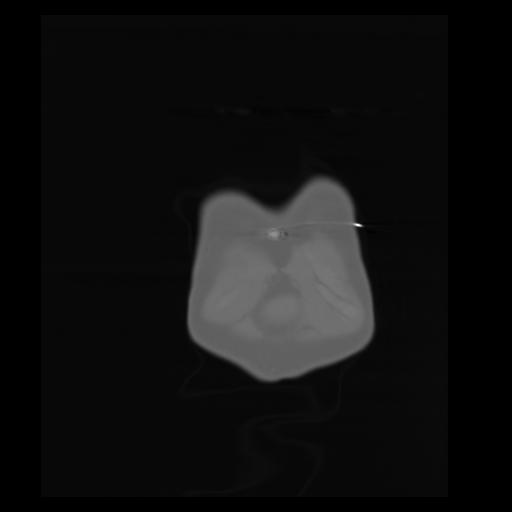

29 CUERPO,CE,Coronal,3.000,CUERPO,Coronal,